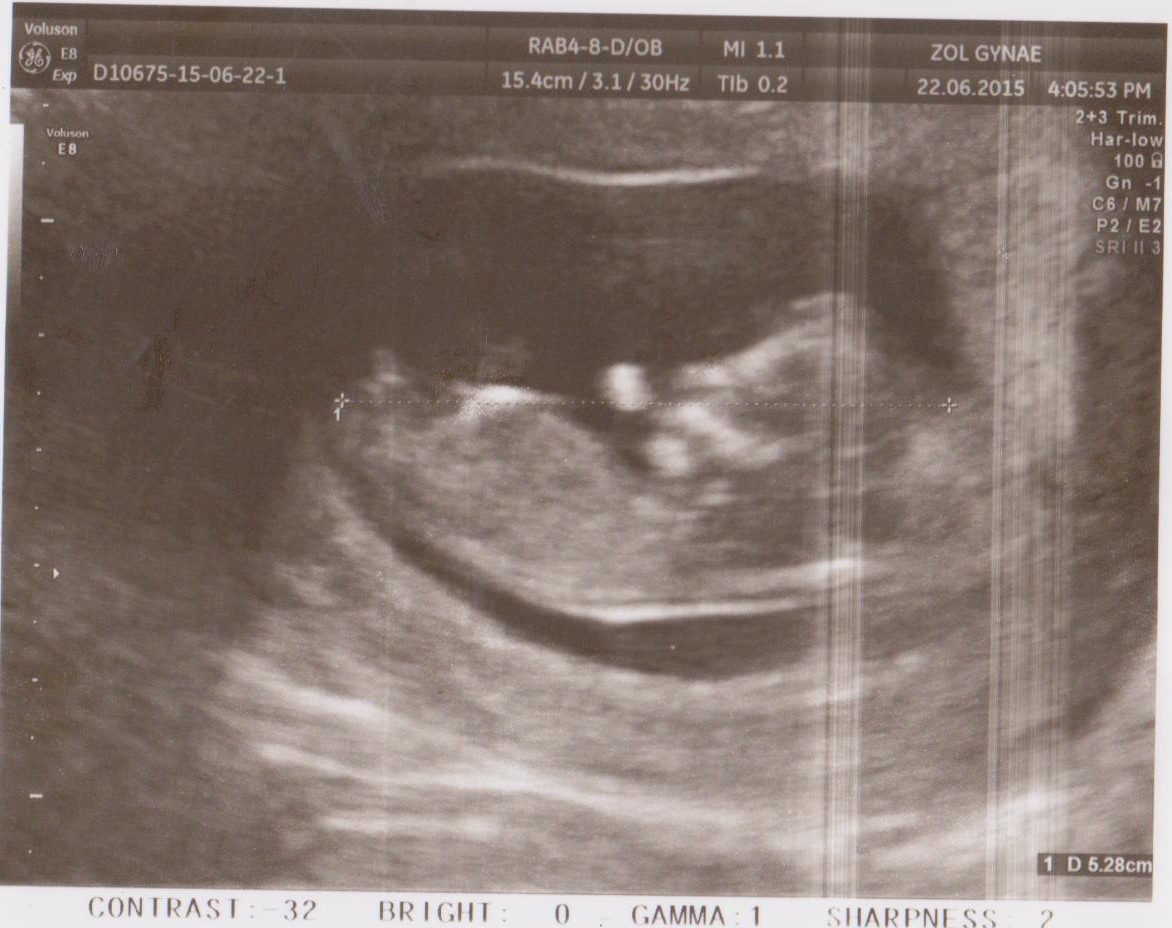

This is my u/s from 12w1d.What you think?Is it defenitly a boy?On the bottom is a clear nub?Thank you for helping. :)

It's still very early, but if that's the nub I'm seeing, leaning boy.

Looks like a perfect boy nub

Looks like a stacked boy nub but could be wrong! xx

Text book Boy! Congrats!